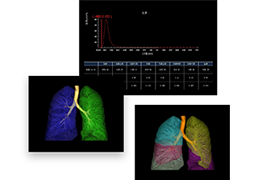

成像智能。

Eclipse 成像智能功能提供强大的处理能力和最佳质量的影像,同时减少质量错误并提高剂量效率。

凭借 AI、专有算法和先进的影像处理能力,提供出色的影像质量和无与伦比的诊断信心。